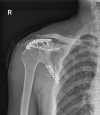

Fracture of the scapular neck combined with rotator cuff tear: A case report

Case summary: A 62-year-old man was admitted to our emergency department 6 h after his right shoulder and back were impacted by heavy objects. The patient presented chest tightness and shortness of breath. Chest computed tomography (CT) showed pneumohemothorax, multiple rib fractures, and right scapula fractures. Three-dimensional CT reconstruction of the right shoulder joint showed a trans-spinous scapular neck fracture with a glenohumeral joint dislocation. Rotator cuff injury was suspected because the patient had a glenohumeral joint dislocation and was then confirmed by shoulder magnetic resonance imaging. A staged surgery was performed, including open reduction and internal fixation of the right scapula fracture and repairing of rotator cuff by right shoulder arthroscopy. At the 5-mo follow-up, the fracture line was blurred and the shoulder joint function was good.